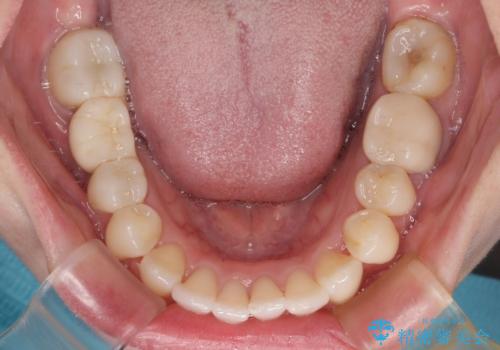

ワーキングホリデー前にきれいな歯列に

- 2、3年後にワーキングホリデーで海外に行くため、その前に歯列やむし歯をきれいにしたいとのことで来院された患者様です。

抜歯の必要な右上の奥歯は事前に抜歯をし、インビザラインにて上下歯列を整えることとしました。

矯正治療後半に奥歯の補綴治療が必要な歯にはオールセラミッククラウンを装着し、インビザラインで最終的に仕上げることとしました。

海外に行く前に口腔内環境を整えることができ、患者様には大変満足していただきました。